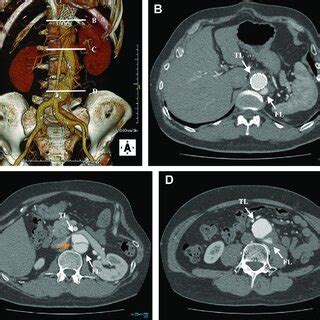

- Preoperative Computed Tomography. A) Threedimensional Reconstruction ...